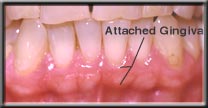

In health, there are two types of gum tissues that surround the tooth. The part that is around the neck of the tooth is firmly attached to the tooth and underlying bone, and is called